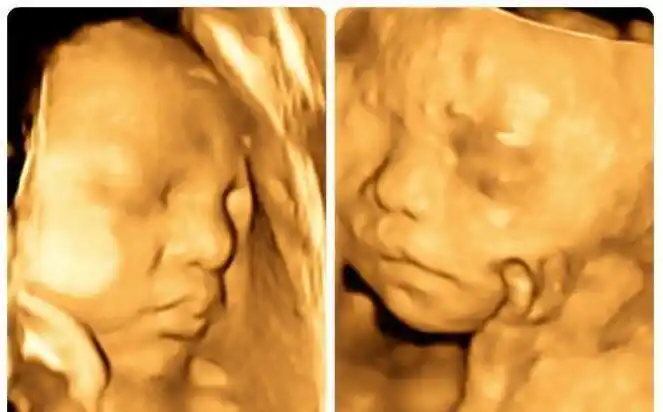

胎儿的四维照片,跟实际相貌有区别吗?